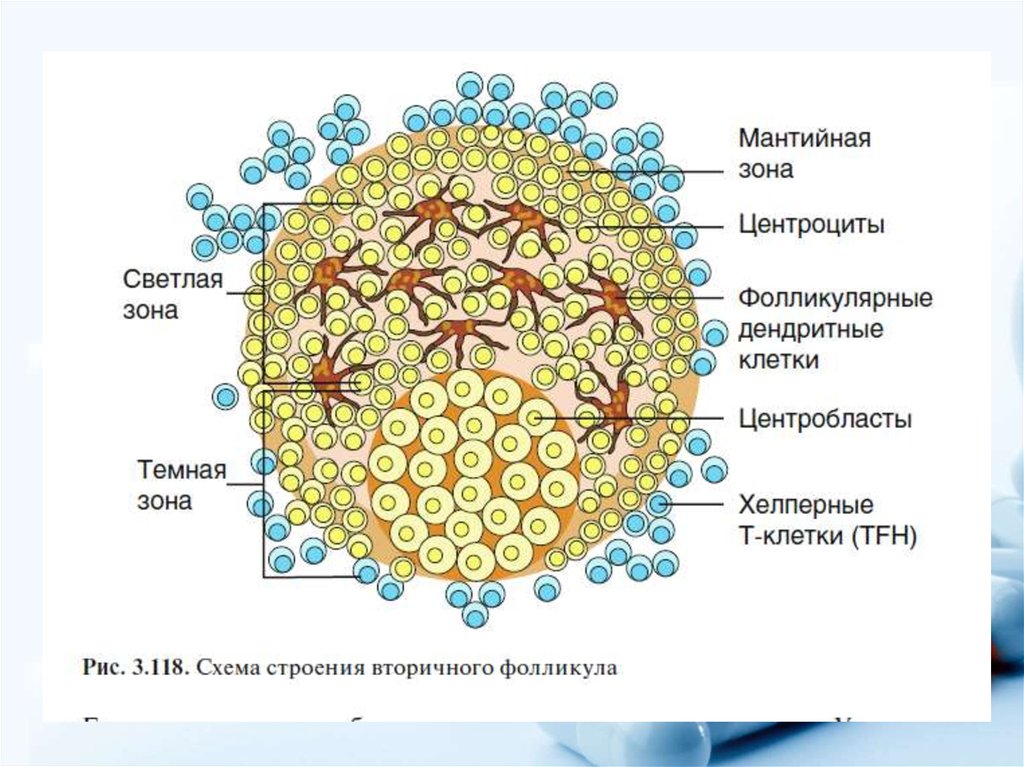

Созревание фолликула в яичнике: этапы и процессы